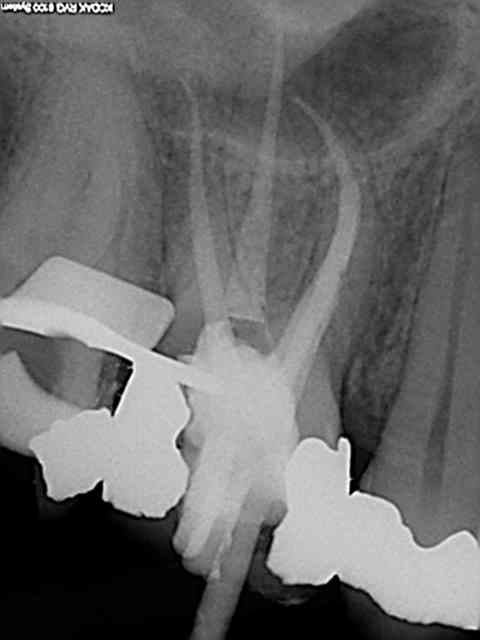

40 mn canal palatin xxl !

Merci. 3 récapitulations s1-r25 pour arriver au bout. je n'ai jamais vu un instrument aussi efficace que le r25, on croirait une ampliation au 50, en insistant un peu il n'y a plus de racine ! )))

Ton matériau d'obturation est confiné dans l'endodonte, je ne vois pas de dépassement de gutta, tes cones sont bien ajustés, je ne vois pas de déchirement apical.